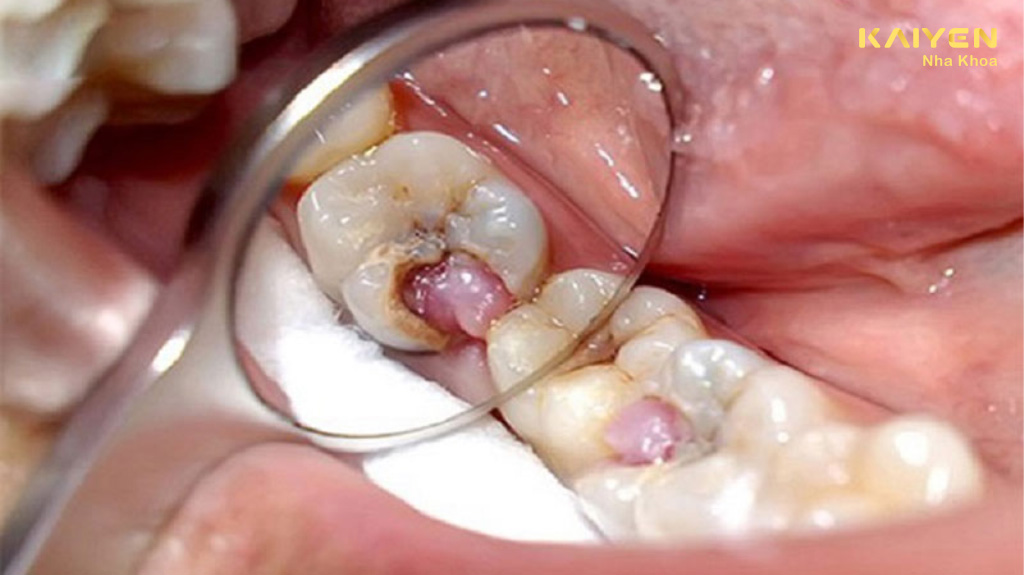

Sâu răng lồi thịt là tình trạng sâu răng ở mức độ nghiêm trọng với sự xuất hiện của hiện tượng viêm nhiễm, áp xe. Hơn thế, khi bị răng sâu lồi thịt, điều này đồng nghĩa với việc bệnh lý sâu răng đã bước vào giai đoạn tủy hoại tử, mô mềm xung quanh bị phá hủy, hình thành các ổ viêm nhiễm.

Khi phần nướu xuất hiện một cục thịt dư do sâu răng lâu ngày không được điều trị thì đấy chính là bệnh lý sâu răng lồi thịt. Cục thịt dư này là vùng niêm mạc bị chảy mủ, sưng to. Theo giới chuyên gia, tình trạng này còn được xem là một loại áp xe răng, làm ảnh hưởng đến tủy, thậm chí làm chết tủy.

Phần nướu bị vi khuẩn tấn công dẫn đến thối rữa, hoại tử và tạo ra lỗ dò. Sau đó, phần niêm mạc quanh lỗ dò sẽ viêm nhiễm nặng, sưng tấy và trồi ra ngoài với hình dạng trông như cục thịt.